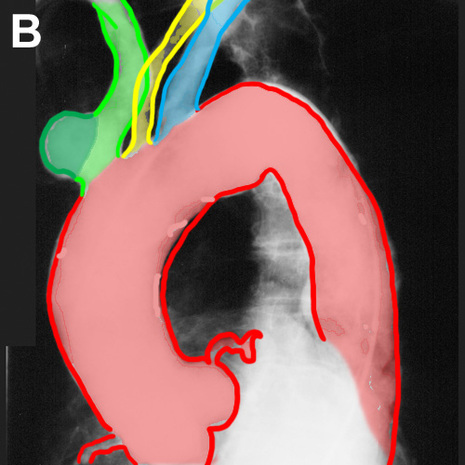

Image B shows the aortic arch and its branches outlined:

The aorta is outlined in red. The first branch, the brachiocephalic artery, is shown in green. There is a rounded outpouching near the origin of this vessel that protrudes from the anterior side of the vessel. A contour abnormality of this type is called a saccular aneurysm, and in this patient this abnormality was visible on the lateral chest radiograph, simulating an anterior mediastinal mass. The normal left common carotid artery is shown in yellow and the normal left subclavian artery is shown in blue.